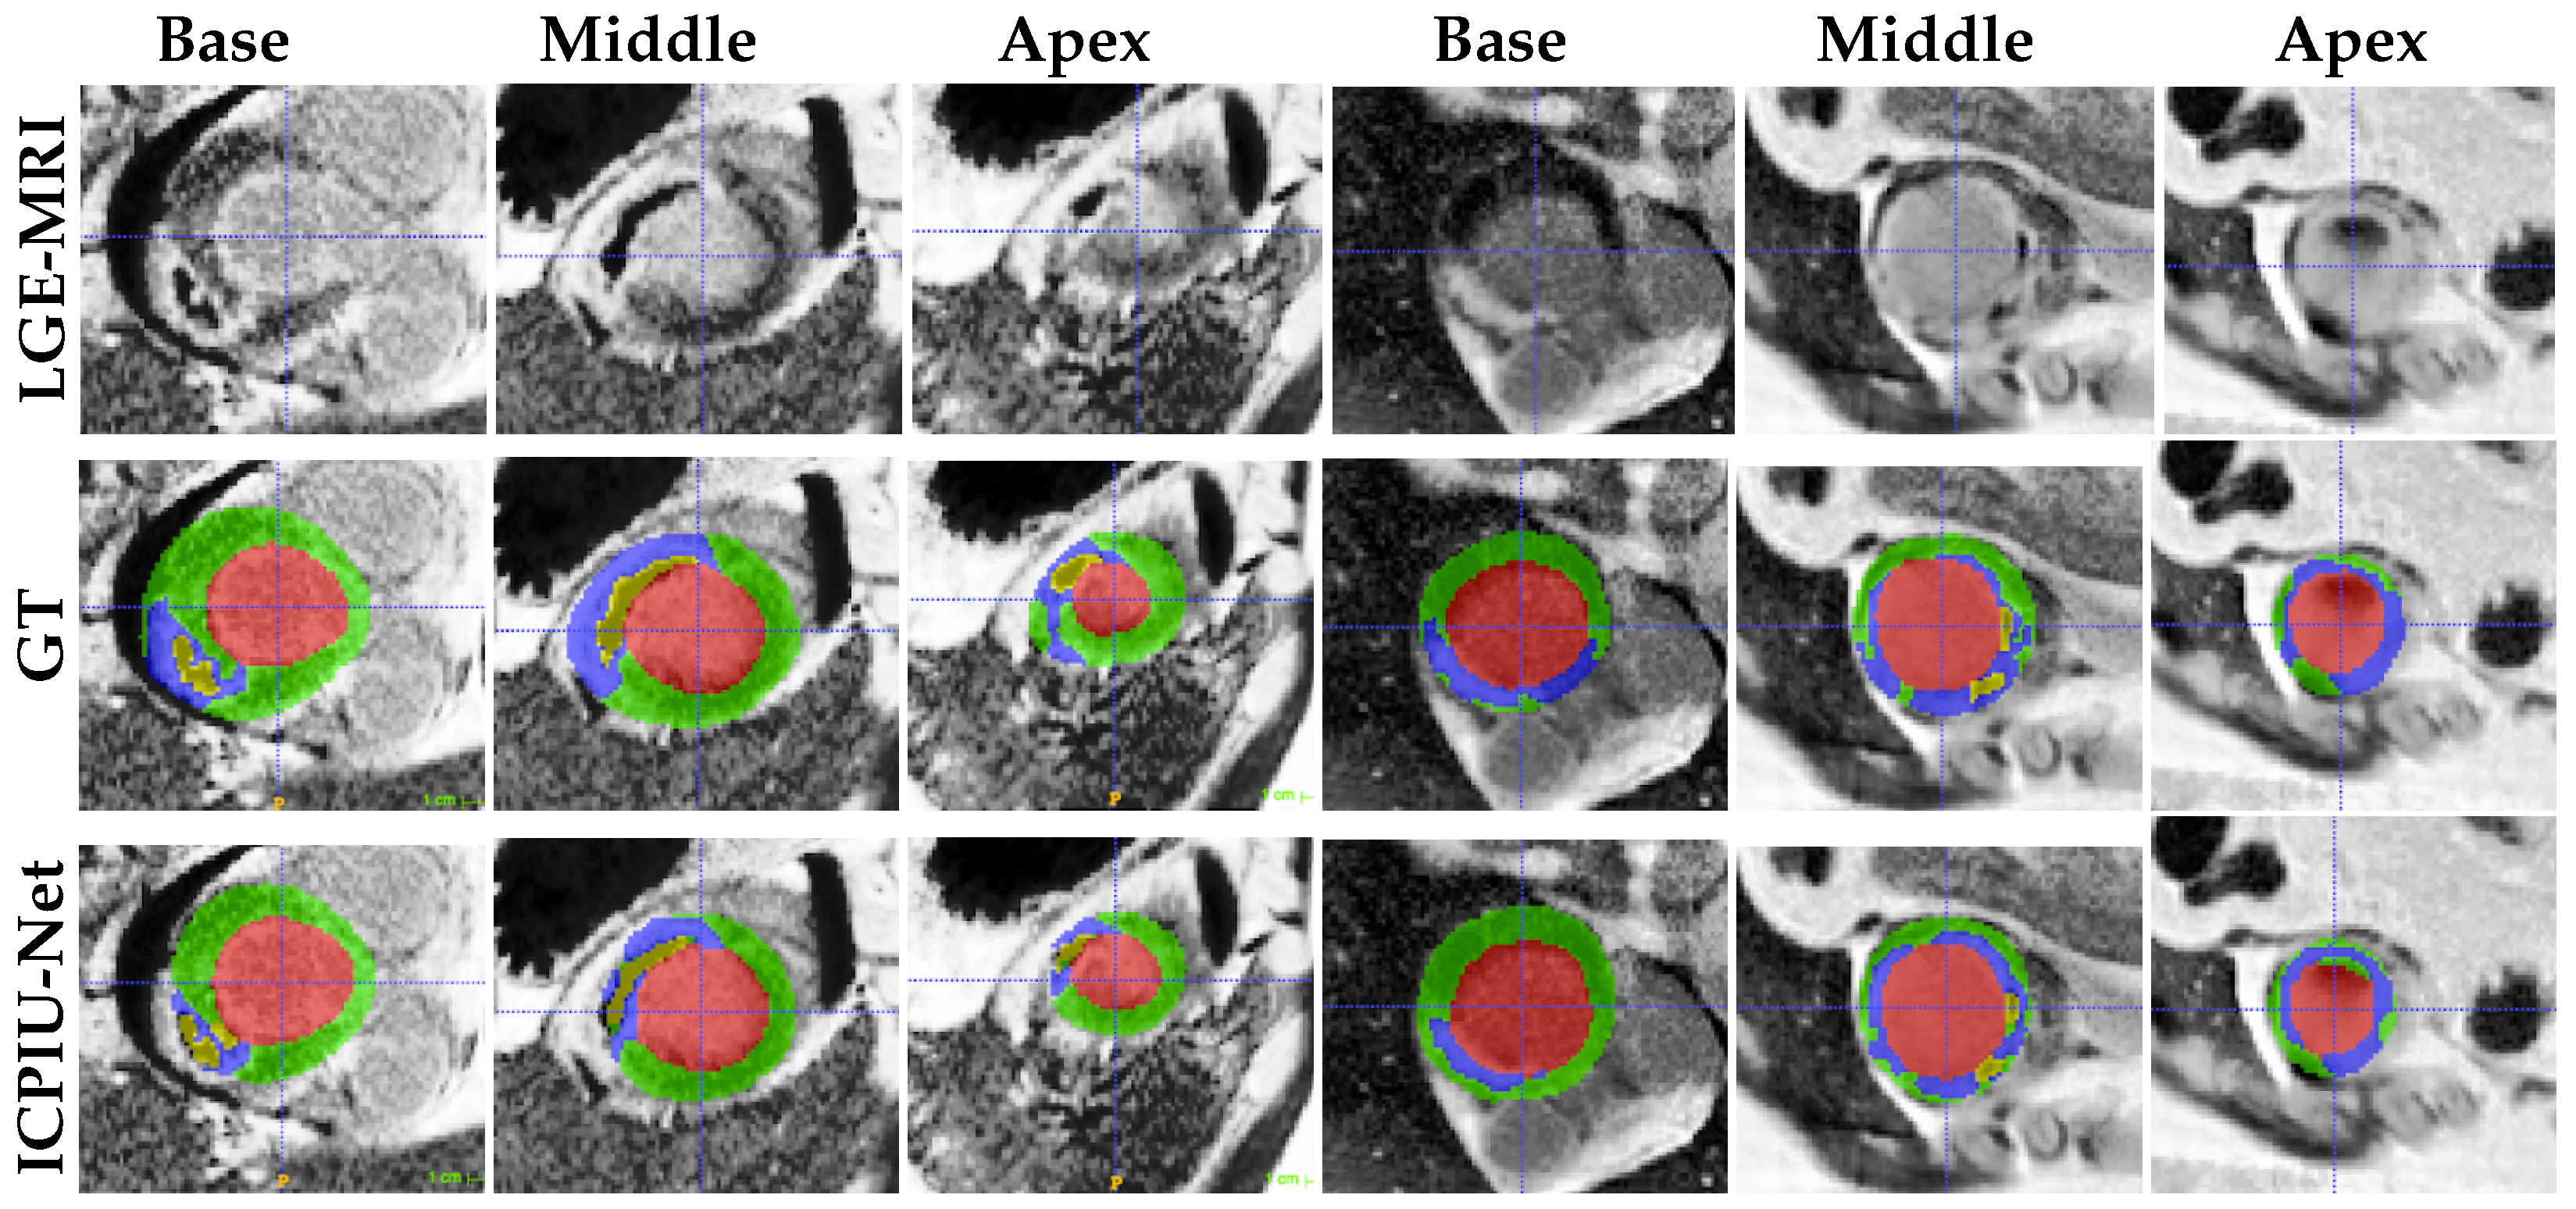

Figure 6 shows segmentation results of EMIDEC challengers, ground truth mask, and our proposed ICPIU-Net for all slices, chosen from one patient of the testing dataset. Visually, our proposed network correctly depicted myocardial structures and showed a good agreement with the gold standard. In comparison to Zhang’s method, our approach demonstrated promising performance in segmenting the damaged myocardial areas from LGE-MRI.

As shown in Figure 7, qualitative evaluations demonstrate that our proposed network accurately segments infarcted patients, especially at the middle slices. The segmentation results achieved by our proposed ICPIU-Net approach are coincident with the expert delineations for both two volumes. Most segmentation errors appear at basal and apical short-axis slices.

Figure 6. Segmentation results and the ground truth mask on Case 119. (a) LGE-MRI, (b) Ground Truth, (c), Zhang [47], and (d) ICPIU-Net.

Figure 7. Examples of test segmentation results and ground-truth for three different levels (base, middle, and apex) of two patient slices (columns 1–3 from patient 1 and columns 4–6 from patient 2). Red: LV cavity, Green: LV myocardium, Blue: Infarct, and Yellow: MVO.